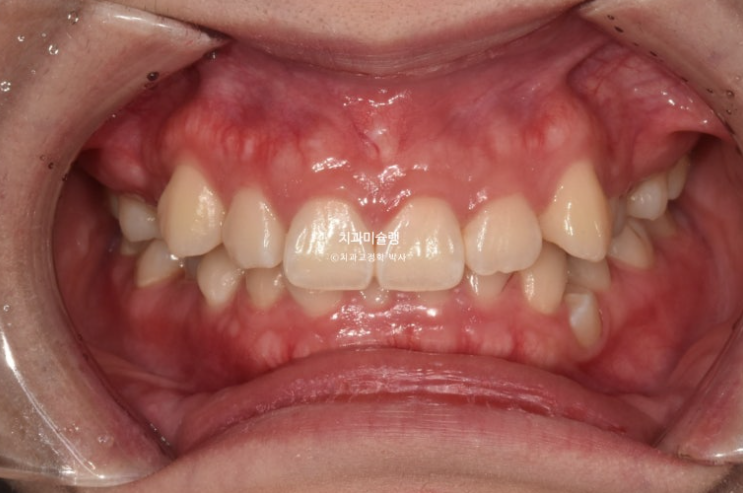

2년 전 교정치료를 위해 온 20대 환자분 입니다.

중심선이 약 2mm 어긋나 있으며 송곳니 덧니가 보입니다.

위 아래 앞니가 깊게 물리는 과개교합도 보입니다.

웃을때 잇몸이 많이 보이는 거미스마일이 있습니다. 특히 위 앞니가 뒤로 쓰러진 옥니 입니다.

작은어금니 하나가 매복되었다시피 깊게 누워있습니다.